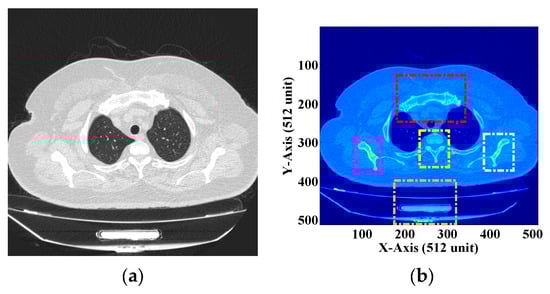

The image is extracted from the software and presented in Figure 11a. The image consists primarily of two types of information, i.e., helpful information and redundant information. Valuable information is stored in the ROI, which consists of vital data about the parts of the body infected with the virus. Redundant information includes the region of the body is unaffected by the virus, which becomes unimportant from a diagnostic point of view. This redundant information is stored in the NROI region. An image under investigation can have a single or several diagnostic vital regions. These ROIs can be compressed losslessly or can be kept as is according to one’s needs. Since these are medical images, they need to be handled very carefully, and storage space reduction becomes the secondary objective while treating these images.

Figure 11.

(a) DICOM image of the human chest [55] (b) ROI selection from the DICOM image.

Figure 11a shows the DICOM image of the human chest with the ROI and NROI together. This image consists of too much redundant information. Let us assume that Figure 11b shows the DICOM image with four different ROIs represented by four different colors. These ROIs are considered necessary from the diagnostic point of view. These subsections are square and can be described in matrices. Thus, “lossless” or “no compression” can be applied to these regions of the DICOM image. The rest of the image is considered as the NROI, which does not have any useful information and thus can be compressed using any lossy compression technique. In this “process development”, a DICOM image with a single ROI is assumed, and the proposed methodology is implemented. A single ROI can be of any dimension, size, and shape, but the ROI used in our experiment is square.

Figure 12a represents the DICOM image with a single ROI. The ROI consists of the most vital information from a “diagnostic point of view”. The ROI can be considered an essential region consisting of information about disease. Thus, in the entire DICOM image, the ROI needs to be handled with a lot of care. This region can be compressed using “lossless compression” or “no compression”. The ROI is extracted from the DICOM image using the “sectioning technique” available in the Matlab software (R2023a). A square section of dimensions is extracted from the DICOM image, as shown in Figure 12b. It can be observed that the size of the ROI is different from the original DICOM image. Thus, any matric-based mathematical operation cannot be performed. Therefore, the zero-padding technique is applied to the ROI to create an image matrix having dimensions . In the zero-padding approach, every matrix position is filled with “zero”, leaving the ROI, and a matrix of desirable dimensions is created. This step is performed so that matrix differencing can be achieved to obtain the NROI from the DICOM image. The zero-padded image with the same dimension as the original image is presented in Figure 13a. The zero-padded image is subtracted from the original DICOM image, and the resultant image obtained after subtraction is illustrated in Figure 13b. This image does not contain any helpful information from the diagnostic point of view and is considered as the NROI. Thus, this region can be compressed using various lossy compression techniques according to one convenience and application.